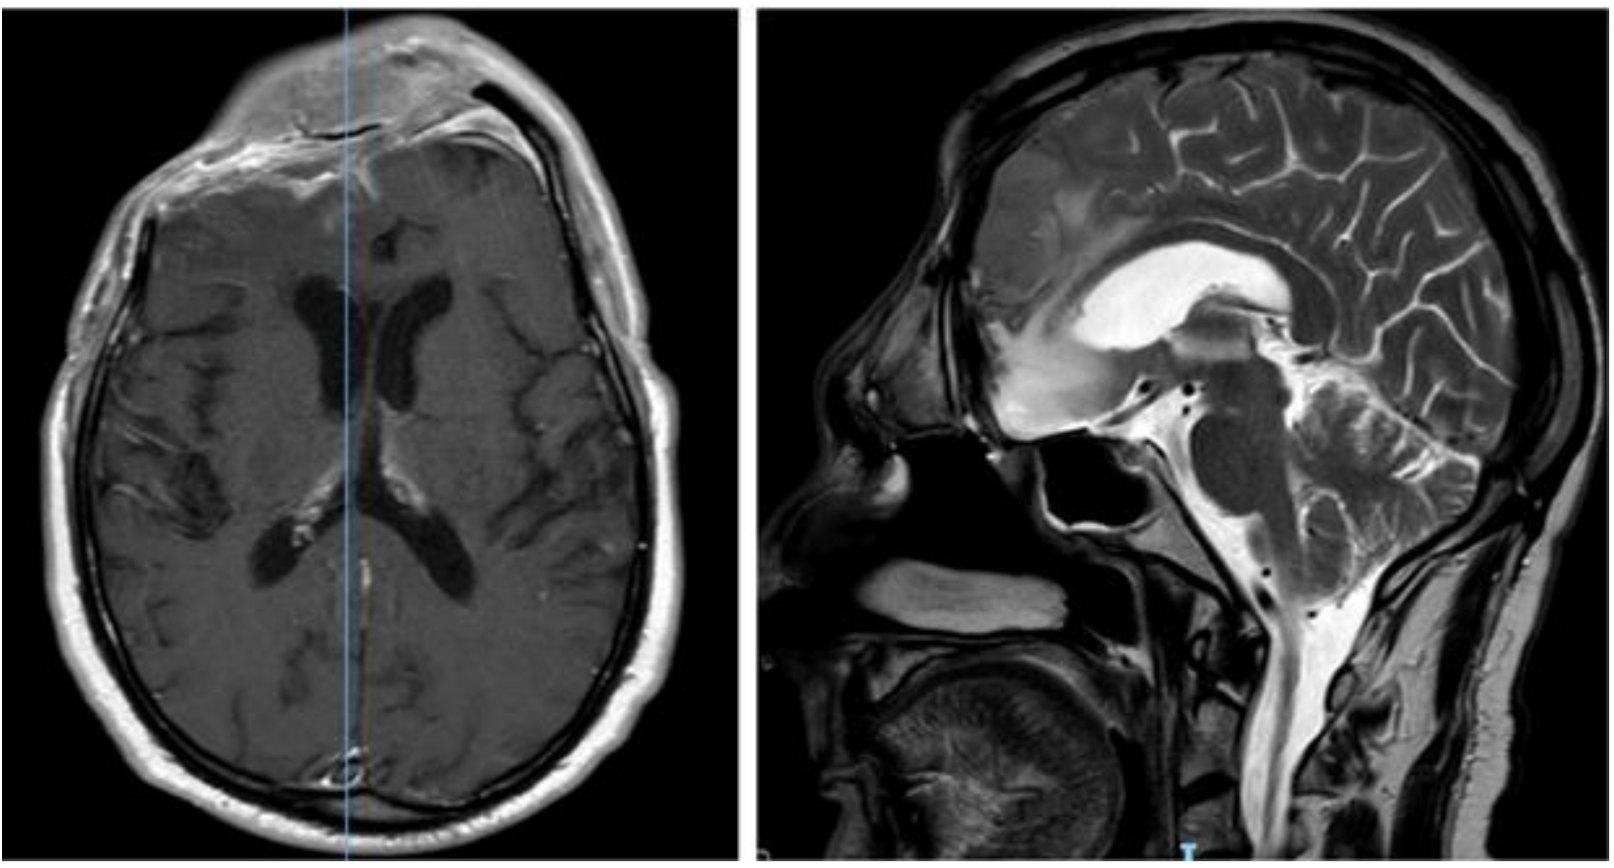

The CT scan showed removal of tumor and empyema and the appearance of pneumocephalus (Figure 5). A few days later and after antibiotic therapy, we performed a combined right frontal craniotomic and transsphenoidal endoscopic rescue procedure with fascia lata to seal off the cranial base from nose cavity. The post-operative CT scan showed the persistence of pneumocephalus with mass effect. Six days later, we performed a new intervention in collaboration with plastic surgeons: a chimeric perforator anterolateral thigh (ALT) free flap including a superficial monitor skin paddle and a portion of rectus femoris muscle was used to close the spheno-ethmoidalis defect (Figure 6 and Figure 7). The post-operative MRI showed the resolution of the pneumocephalus, and the patient was discharged with no neurological symptoms.

Figure 6.

Post-operative brain MRI after evacuation of the epidural empyema, cranial bone flap removal and reconstruction by means of anterolateral thigh flap.